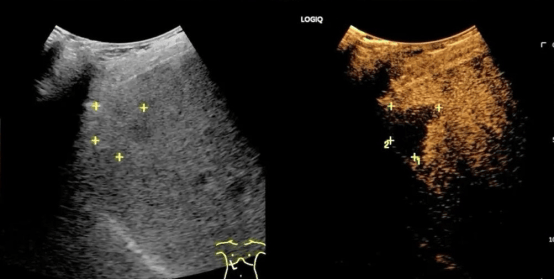

2.超声定位:术者将在超声下为患者精准确定穿刺点和穿刺路径,标记肿瘤位置;

图为我院肿瘤内科开展消融手术现场

术前

术后